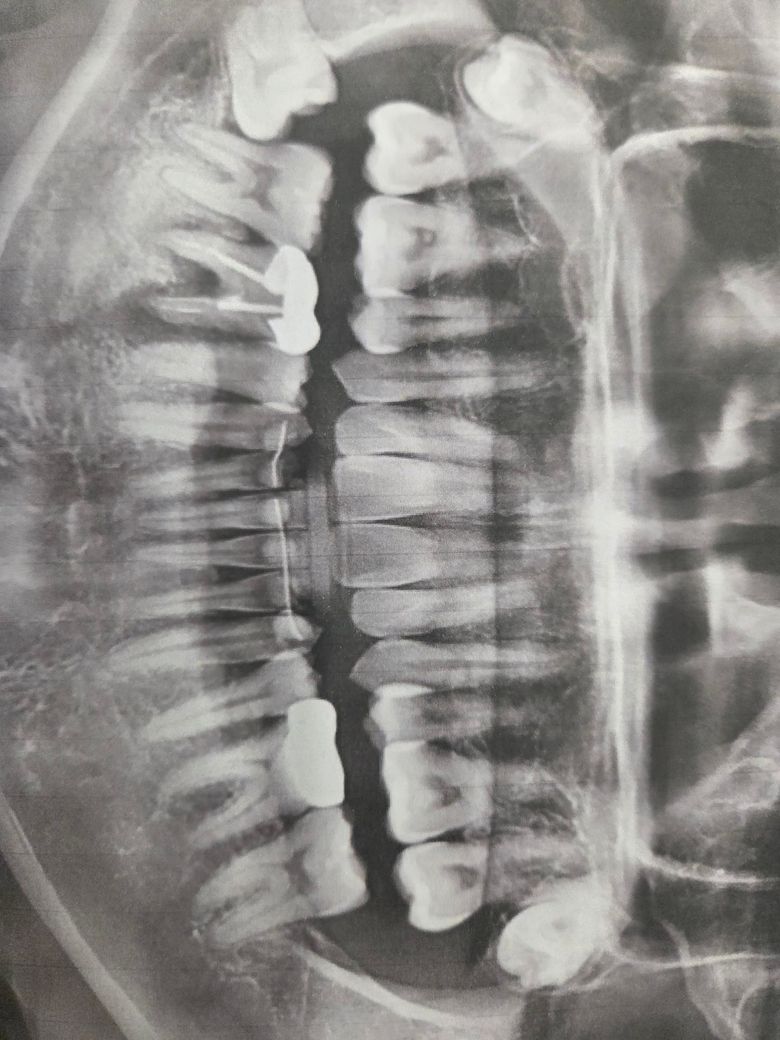

뼈가 썩어 발치후 뼈이식 임플란트해야한다는데 맞을가요

치아 오른쪽 사랑니옆이 뿌리가 다 썩어서

발치후 뼈이식후 임플란트해야하는데

사진으로 봤을 경우 오른쪽아래 어금이 뿌리 부위의 골결손이 심한것으로 보입니다.

발치후 잇몸이 아무는 시간이 필요할것으로 보이며 경우에 따라서는 골이식이 필요할수 있습니다.

46번 (오른쪽 아래 첫번째 큰 어금니) 은 신경치료를 했지만 염증이 완전히 해소되지 않은 것 같습니다. 뼈가 염증으로 녹고 있고, 재신경치료 내지는 발치 후 임플란트 고려해봐야 합니다. 임플란트 시 뼈이식 필요할 수도 있고요.

그 옆 47번도 상태는 좋아보이진 않고, 신경치료 가능성 있습니다.